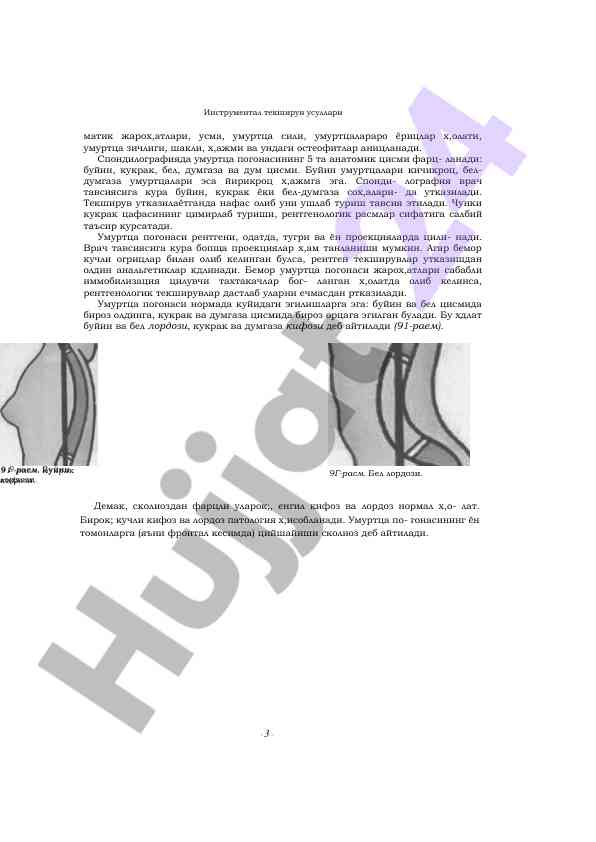

Rengtenologik tekshiruvlar neurodiagnostikada muhim ahamiyatga ega. Ushbu maqola rengen tekshiruvlarining tibbiyotdagi o'rni va usullarini o'rganadi.